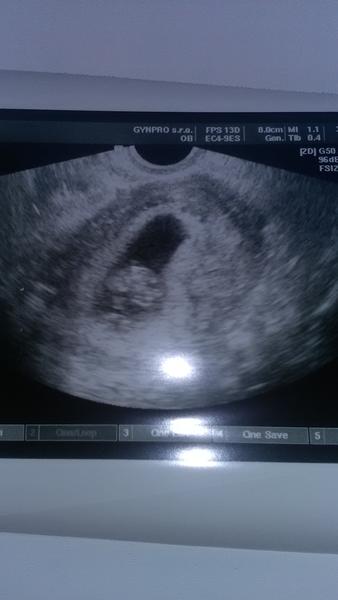

Ahoj holky, dnes jsem byla u Dr., podle Utz jsem 6+2 a uz nam krasne bije srdicko. Na dalsi kontrolu jdu az za mesic, pristi tyden letime na dva tydny na Maledivy, tak snad tam bude vse v poradku. Holky, ja se tak moc tesim! 🙂